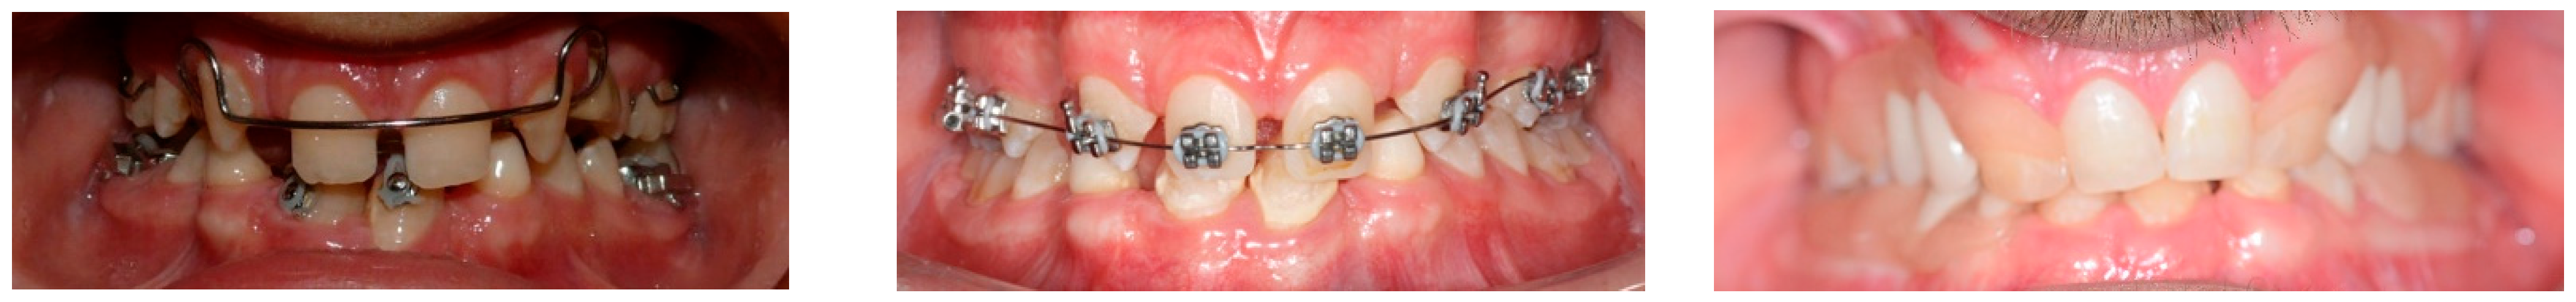

- Celli, D.; Manente, A.; Grippaudo, C.; Cordaro, M. Interceptive treatment in ectodermal dysplasia using an innovative orthodontic/prosthetic modular appliance. A case report with 10-year follow-up. Eur. J. Paediatr. Dent. 2018, 19, 307–312. [Google Scholar] [CrossRef] [PubMed]

- Cerezo-Cayuelas, M.; Pérez-Silva, A.; Serna-Muñoz, C.; Vicente, A.; Martínez-Beneyto, Y.; Cabello-Malagón, I.; Ortiz-Ruiz, A.J. Orthodontic and dentofacial orthopedic treatments in patients with ectodermal dysplasia: A systematic review. Orphanet J. Rare Dis. 2022, 17, 376. [Google Scholar] [CrossRef] [PubMed]